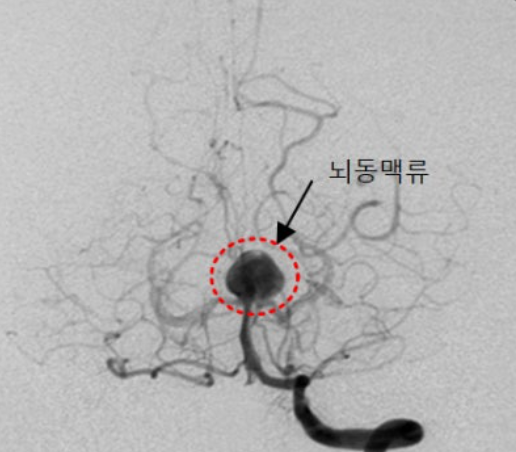

뇌동맥류(Cerebral Aneurysm)는 뇌혈관 벽의 일부가 약해져 꽈리처럼 부풀어 오르는 질환입니다.

마치 낡은 타이어에 공기가 과하게 들어가 부풀어 오른 모습과 비슷하다고 생각하시면 됩니다.

이렇게 부풀어 오른 뇌동맥류는 언제든지 파열될 수 있으며, 파열될 경우 뇌출혈로 이어져 생명을 위협하거나 심각한 후유증을 남길 수 있습니다.